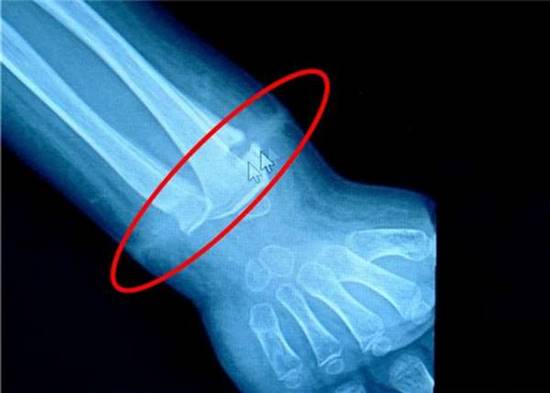

วันที่ 17 มิถุนายน 2559 เว็บไซต์เดลี่เมล เปิดเผยเคสผ่าตัดชวนตะลึงจากเมืองจีน เด็กชายหลงหลง วัย 4 ขวบ เข้ารับการรักษาอาการอักเสบที่ข้อมือ ซึ่งก่อนหน้านี้แพทย์รักษาตามอาการแต่ก็ไม่หายขาดสักที กระทั่งแพทย์ตัดสินใจเอกซเรย์และผ่าตัด จึงพบว่ามีหนังยางรัดเนื้อข้อมืออยู่ภายใน

กระทั่งวันที่ 8 มิถุนายนที่ผ่านมา ข้อมือของเด็กชายเกิดบวมขึ้นมามากกว่าเดิมหลายเท่า คราวนี้แพทย์จึงต้องรีบผ่าตัดเด็กชายโดยด่วน และก็ต้องพบกับเรื่องสุดตะลึง เมื่อผ่าตัดข้อมือแล้วพบว่ามีหนังยางอยู่ภายใน